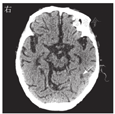

患者男,79岁,因"咳嗽、咳痰8 d,发热3 d"于2020年9月7日收入南京中医药大学附属南京中医院感染性疾病科。患者8 d前无明显诱因出现阵发性咳嗽、咳痰,痰色黄、质黏、难以咳出,伴气喘。3 d前,患者出现发热,最高体温达38.4 ℃,伴大小便失禁及呕吐胃内容物1次,至南京中医药大学附属南京中医院急诊科就诊。查血常规示白细胞计数为23.70×109/L,中性粒细胞比例为0.913,血红蛋白为134 g/L,血小板计数为210×109/L,CRP为73 mg/L。胸部CT检查示两肺气肿伴肺大疱形成,两肺间质性改变;左肺上叶团片影,考虑炎性病灶可能(图1A)。患者既往有心房颤动、心功能不全、慢性阻塞性肺疾病病史;有未分化结缔组织病病史1年余,长期服用泼尼松和雷公藤,泼尼松用量为5 mg/次,2次/d。入院后体格检查:体温为36.5 ℃,心率为75次/min,呼吸为20次/min,血压为98/62 mmHg(1 mmHg=0.133 kPa)。神志清楚,精神萎靡,淋巴结未及肿大。桶状胸,双肺呼吸音减弱,双下肺可闻及少量细湿啰音。心律不齐,未闻及病理性杂音。腹软,无压痛及反跳痛。双下肢无水肿。实验室检查示CRP为160 mg/L;ESR为102 mm/1 h;降钙素原为11.54 μg/L;脑钠肽为2 684 ng/L;铁蛋白>1 650 μg/L;白蛋白为19 g/L;EB病毒、CMV、β-D-葡聚糖试验、半乳甘露聚糖抗原试验、T细胞亚群、免疫五项(IgA、IgG、IgM、补体C3、补体C4)检查、T-SPOT.TB和PPD结果均为阴性。一般细菌痰涂片、痰涂片找抗酸杆菌、真菌涂片检查结果均为阴性。结合既往病史、辅助检查,考虑肺部细菌、真菌感染均不能排除,故予比阿培南(300 mg/次,4次/d)联合伏立康唑(200 mg/次,2次/d)静脉滴注抗感染治疗。9月14日(入院第8天)患者体温恢复正常,咳嗽、咳痰较前好转,胸部CT检查示肺部病灶较前吸收(图1B),血培养结果为乔治教堂诺卡菌阳性(图2),加用复方磺胺甲噁唑(磺胺甲噁唑/甲氧苄啶,800 mg/160 mg, 2次/d)。9月18日完善腹部和头颅MRI检查,结果回报左侧颞叶异常信号,考虑脓肿可能(图3A),余脏器未见血行播散病灶。患者感染乔治教堂诺卡菌,血行播散至脑形成脓肿,播散性诺卡菌病诊断明确,改用头孢曲松(2 g/次,2次/d)静脉滴注联合复方磺胺甲噁唑(2次/d)口服抗感染治疗1周后复查,血常规示白细胞计数为5.90×109/L,中性粒细胞比例为0.821,CRP<1 mg/L。患者临床症状和炎症指标较前明显好转,9月30日出院后序贯口服复方磺胺甲噁唑(2次/d)联合利奈唑胺(600 mg/次,2次/d),治疗10 d后复查血培养结果为阴性,10月14日复查头颅MRI示脑脓肿较前吸收(图3B)。10月27日复查头颅CT,提示病灶较前明显好转(图4)。2021年2月19日患者复查血培养结果为阴性,胸部CT检查示病灶较前吸收(图1C),头颅MRI检查示病灶已吸收完全,予复方磺胺甲噁唑减量(磺胺甲噁唑/甲氧苄啶,400 mg/80 mg, 3次/d)。